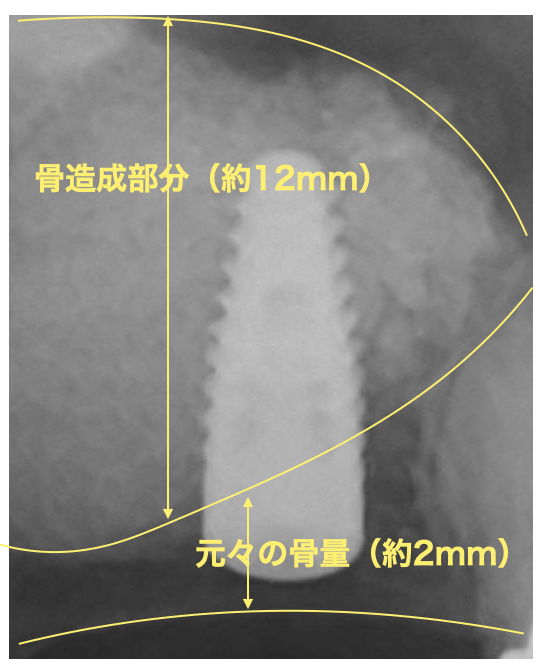

右上奥歯にインプラントを希望して来院されました。他院では骨がないためインプラントは出来ないと言われたとのことでしたが、サイナスリフト(上顎洞底挙上術)を行うことで骨の高さが3mmから14mmまで増加しました。

治療回数:サイナスリフトは一度の手術で終わります。その後インプラントの手術が必要になります。

治療期間:サイナスリフトを行いしっかりした骨が出来るのは約6ヶ月かかります。その後にインプラント治療を行います。

サイナスリフト:¥200,000(税込220,000)

上顎洞底の粘膜を持ち上げて、そこに骨を作る手術になります。粘膜は1mm程度の薄い膜のため持ち上げる際に穿孔(穴が開く)する場合があります。小さい穴であれば閉鎖することが出来ますが、大きな穴が開くと再度手術になる場合があります。術後に腫れ、痛み、出血、感染のリスクがあります。